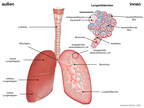

Lunge (Organ, Mensch)

(1024x768)